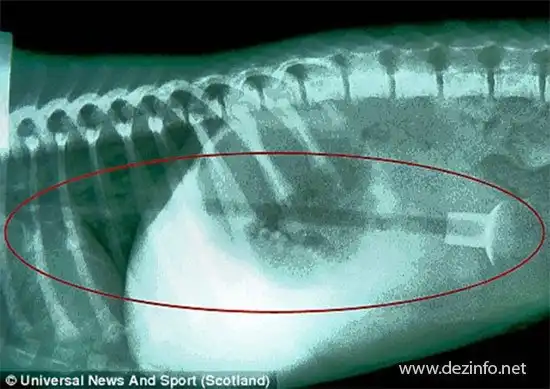

13 камней сожрал 6 месячный лабрадор. Лечение песка обошлось в 1500$.